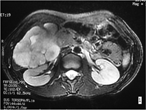

Synchronous contralateral adrenal metastasis of colorectal cancer: case report

Micaela Raices and others

Journal of Surgical Case Reports, Volume 2017, Issue 6, June 2017, rjx098, https://doi.org/10.1093/jscr/rjx098